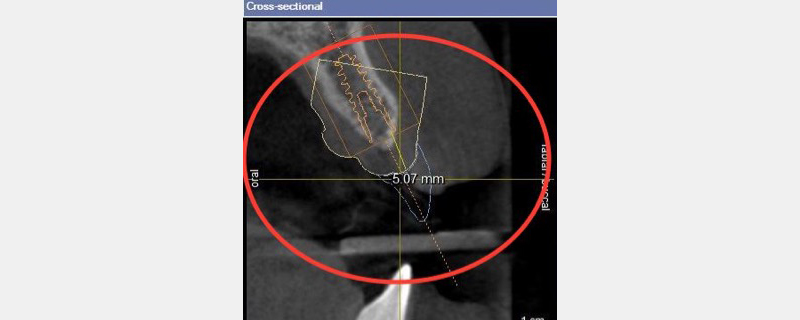

As I show them the merged virtual crown proposal and CBCT, they can see precision and predictability in action. Their anxiety drops, and confidence rises.